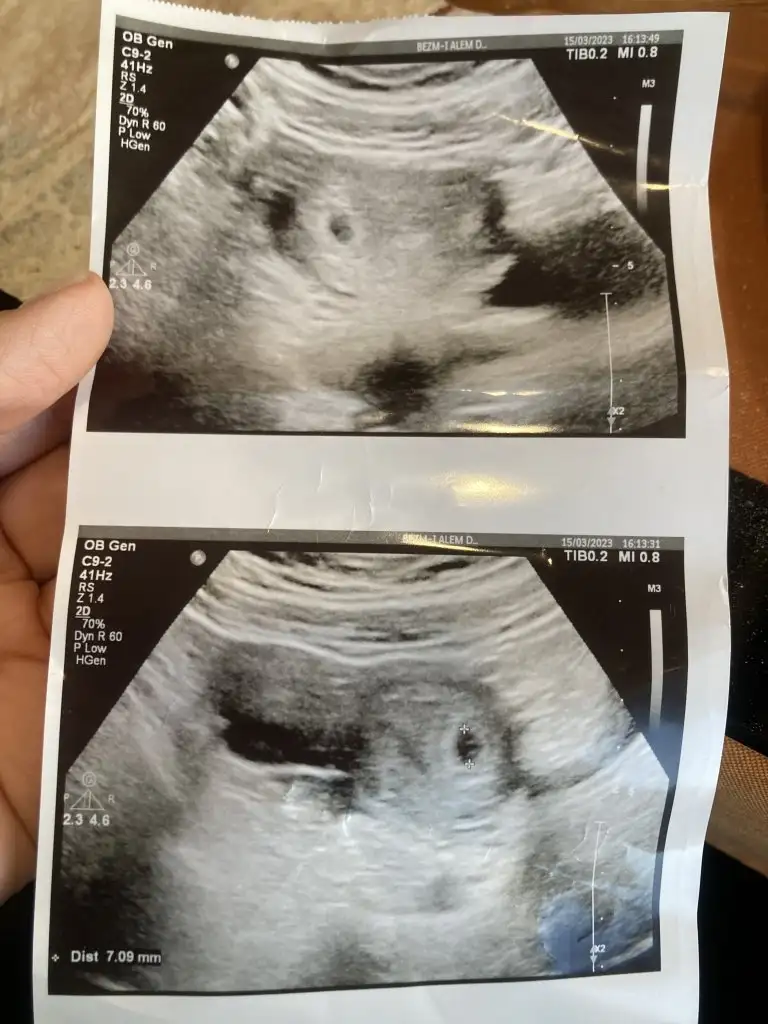

Kızlar bugün doktora gittim sat a göre 6+2 yim fakat doktor 5 haftalık gibi dedi kese içinde bebek gorunmedi zaten haftaya tekrar çağırdı ve gece çok lekelenmem gelmişti kahverengi onun için gittim aslında progestan başladık burda kese yukardaki küçük olan mi asagida olan mi acaba

Dr değilim ne söylesem yalan olur bazen gebelik kisti oluyor bebek beslenmesi için yumurtalık kisti aşağıdaki öyle bişey olabilir mi acaba. Ama kese üstteki bence .